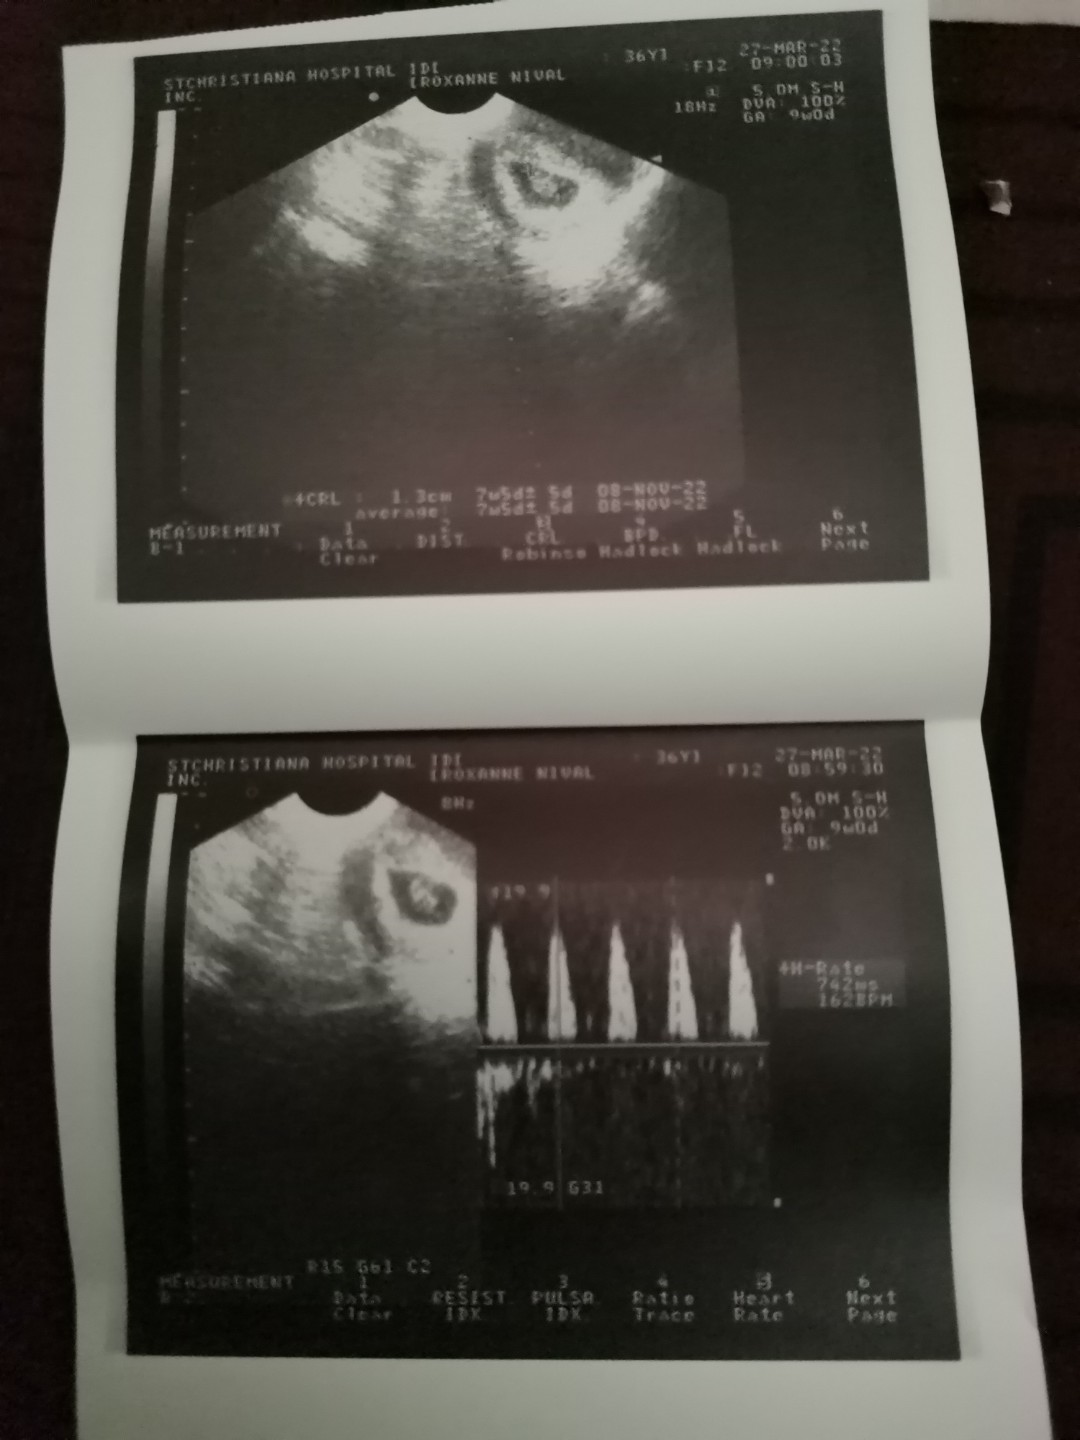

Magbasa pahi po doc pwd po magtanong?ako po kasi 9weeks pregnant,almost 1month na po ako spotting. pero d naman kalakasan..pero minsan pag iihi ako may mga dugo na parang sipon na lumalabas.and ang hb ng baby ko nung last check up ko nung 14 eh 101 lng po..may chance pa po ba na bumilis ang hb nya?and yung spotting gang kelan ko kaya mararanasan. katapusan pa po kasi ang balik ko sa ob..maraming salamat po..by d way im 41 yrs old po